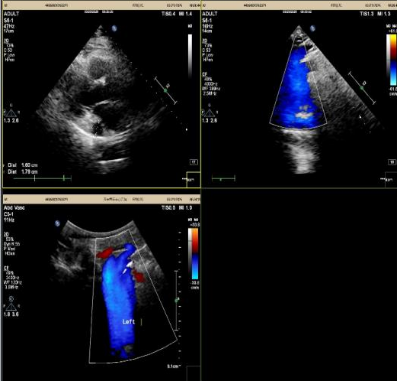

患者的上腔静脉——也就是传统起搏器电极必须经过的主干道——存在罕见的解剖变异。

她得了一种叫「永存左上腔静脉」的先天畸形,发生率只有 0.3%-0.5%。更要命的是,她的右上腔静脉还闭塞了。

张卫泽副院长带领心内一科团队,通过完善血管超声检查精准评估下腔静脉血管路径正常,追踪患者既往心电检查结果确认无房室传导阻滞,与家属商议后决定采用心房无导线起搏器(雅培 Aveir AR)植入术式。